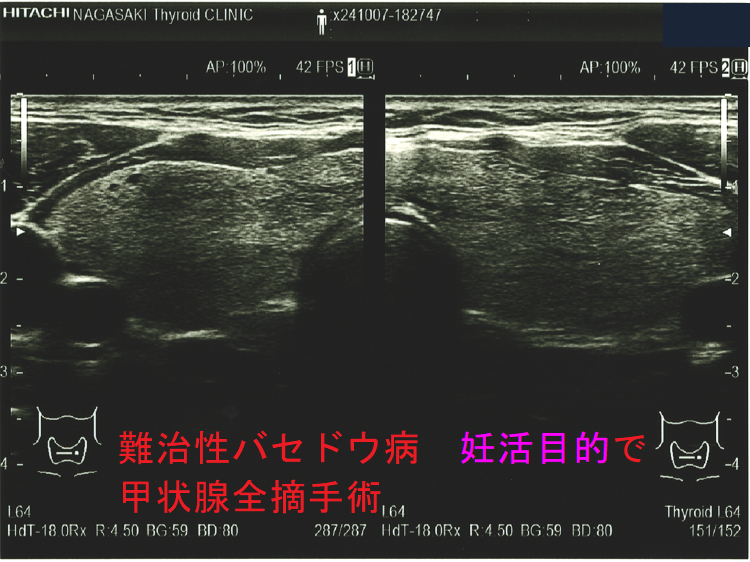

妊娠中、抗甲状腺薬(メルカゾール、プロパジール、チウラジール)+ヨウ化カリウム(KI)でもバセドウ病/甲状腺機能亢進症をコントロールできない時は、もはや妊娠2期(中期)の甲状腺全摘手術になります。[GUIDANCE TO THE MATERNAL, FETAL AND NEONATAL MANAGEMENT OF RESISTANCE GRAVE'S DISEASE IN PREGNANCY. Acta Endocrinol (Buchar). 2021 Oct-Dec;17(4):517-520.]

甲状腺全摘手術すれば母体の甲状腺機能は安定しますが、

- TSHレセプター抗体(TRAb)は急に下がらないため、妊娠20週以降に胎児の甲状腺を刺激して胎児バセドウ病、出生後の新生児バセドウ病の発症を免れません。

- 妊娠3期(後期)の手術だと、母体の甲状腺ホルモンが胎児の脳下垂体にTSH(甲状腺刺激ホルモン)分泌抑制を掛けたままでの出生になり、新生児一過性中枢性甲状腺機能低下症を引きおこす可能性があります。

妊娠中、抗甲状腺薬(メルカゾール、プロパジール、チウラジール)が副作用で使用できなくなった時は、妊娠2期(中期)に甲状腺全摘手術になります。妊娠1期(前期)に使用できなくなった時は、2期(中期)までヨウ化カリウム(KI)で持たせます。妊娠3期(後期)に使用できなくなった時は、出産後までヨウ化カリウム(KI)で持たせます。(第54回 日本甲状腺学会 P199 抗甲状腺薬の副作用のため手術療法を行い出産に至ったバセドウ病合併妊娠の一例)[Obstet Gynecol. 2013 Aug;122(2 Pt 2):490-492.][Korean J Intern Med. 2005 Dec;20(4):335-8.]